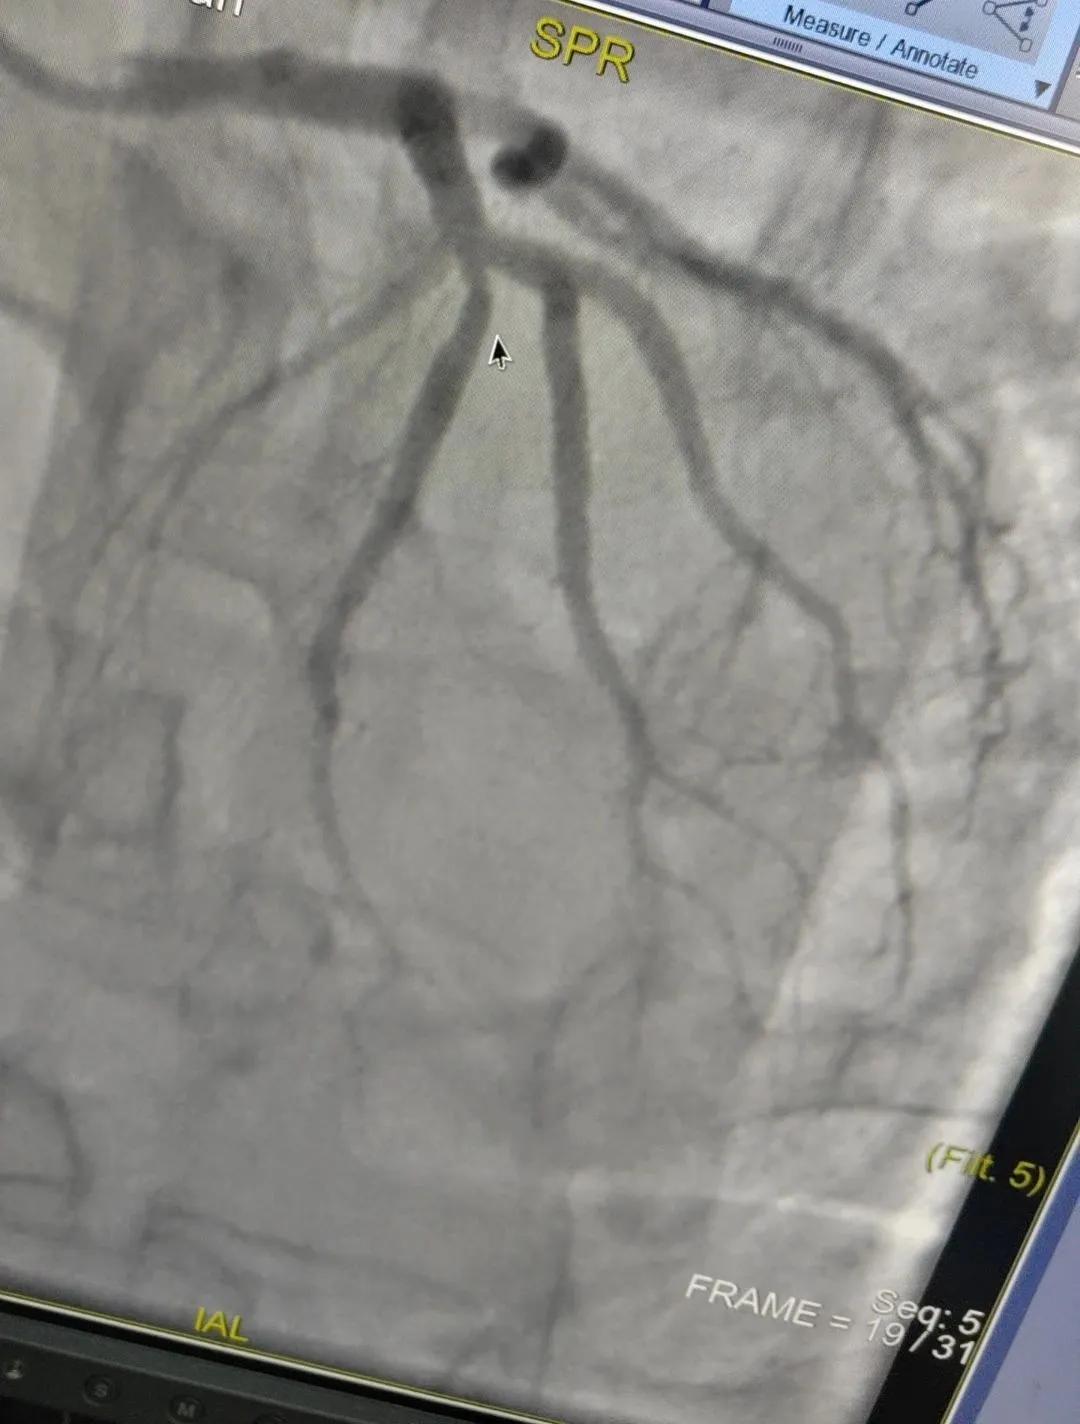

術(shù)中心血管造影顯示:LAD中段發(fā)出D1處可見約50%節(jié)段性狹窄,RCA中段狹窄約40%,PLA可見約70%狹窄病變。

近日,漯河市中醫(yī)院成功開展了一例心腦血管聯(lián)合造影的手術(shù)。

患者男,37歲,兩周前無明顯誘因突發(fā)頭昏,伴右側(cè)肢體無力來院就診,經(jīng)過對(duì)患者病情的評(píng)估以及心內(nèi)科和腦病科醫(yī)生聯(lián)合會(huì)診,需對(duì)患者進(jìn)行心腦血管聯(lián)合造影手術(shù)。由神經(jīng)內(nèi)科楊慶堂副主任與心血管內(nèi)科陳云副主任帶領(lǐng)各自的介入團(tuán)隊(duì)為該患者順利進(jìn)行了全腦血管造影術(shù)+心血管造影的介入檢查。